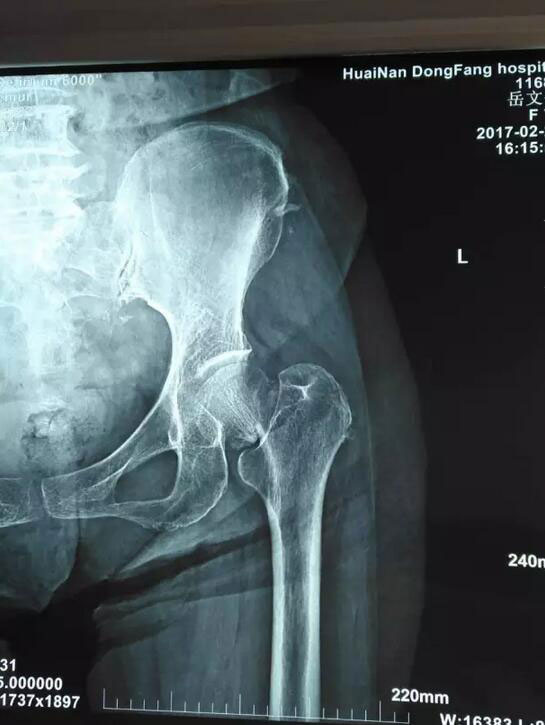

术前术后对比

岳老太太今年已经70岁,因为股骨颈骨折,需要进行全髋关节置换手术。经过总院骨科团队慎重研究并向老太太家属沟通后,3月6日接受了这一最新理念的手术,也是总院骨科开展的第二此类手术。手术由鲁木主任亲自主持,顺利结束后老人安全返回病房。术后第二天,老太太就可以下床并自如行走、弯腰,甚至可以自己穿上袜子,岳老太太的老伴对此惊喜不已,连连对鲁木主任和医护人员们表示感谢。在他的印象中,动了这么大的一个手术,最少要在床上躺上十天半个月,没想到现在恢复的这么快,这么好!一周后,老人恢复良好,顺利出院。